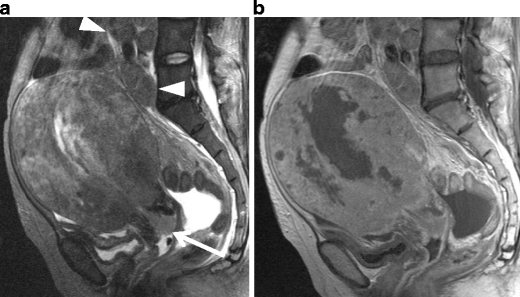

Undifferentiated Endometrial Sarcoma

Undifferentiated stromal sarcoma in a 22-year-old female who presented with acute abdomen due to uterine rupture. a Sagittal T2-weighted image demonstrates an ill-defined myometrial mass of heterogeneous appearance in the anterior wall (arrows). The upper portion of the tumor containing fluid-fluid level represents hemorrhagic necrosis within the tumor (arrowheads). b T1-weighted image demonstrates increased signal intensity corresponding to the area of hemorrhagic necrosis (arrowheads). Hemorrhagic ascites of increased signal intensity also is present in the Douglas fossa and uterovesical fossa (asterisks). c Postcontrast T1-weighted image with fat suppression demonstrates heterogeneous enhancement within the solid component of the tumor (arrows)